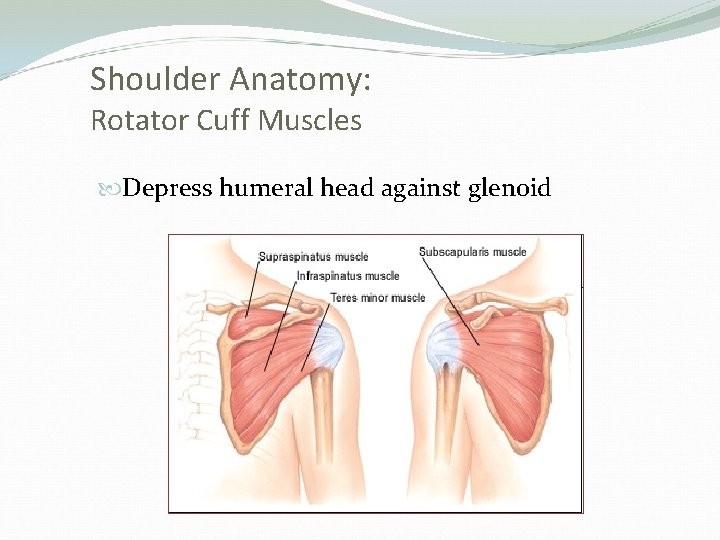

Shoulder Anatomy: Rotator Cuff Muscles Depress humeral head against glenoid

Shoulder anatomy: Rotator cuff muscles Supraspinatus: Abduction Infraspinatus: External rotation Teres Minor: External rotation Subscapularis: Internal rotation